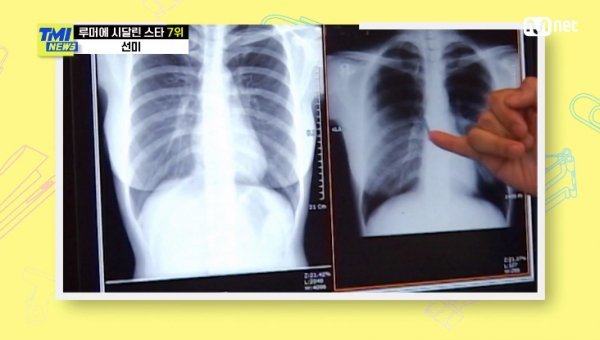

솔로 데뷔 후 자신의 몸매를 드러냈다는 이효리는 핑클 시절 없던 볼륨감에 가슴 수술 의혹이 일어나기도 했단다. 이후 이효리는 자신의 리얼리티 프로그램을 통해 가슴 엑스레이 사진을 공개, 수술을 하지 않았음을 직접 입증했다.